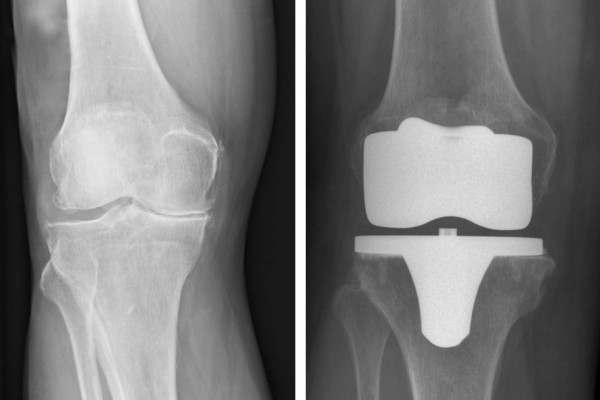

Ersatz des Schulter-, Knie- und Hüftgelenks (TEP)

Die 3 großen Gelenke des Körpers, die Schulter, das Knie und die Hüfte sind leider häufig durch Abnutzung oder nach Unfällen verschlissen. Wenn die konservativen Behandlungsmethoden nicht die gewünschte Linderung bringen, ist manchmal ein Gelenkersatz indiziert.

Dr. M. Matzer verwendet moderne, minimal invasive Techniken zur Implantation von Hüft und Knieprothesen.